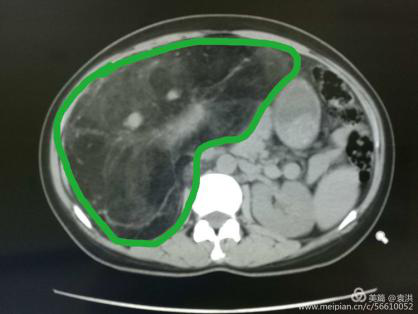

這一檢查讓婦科醫(yī)生也大吃一驚!醫(yī)生檢查時(shí)觸及腹部一硬質(zhì)包塊,無(wú)明顯邊界,上至劍突下,下至盆腔,兩側(cè)至腋中線,無(wú)壓痛,固定,說(shuō)明這包塊占據(jù)了患者整個(gè)腹腔,考慮來(lái)源于其它臟器,立即行全腹CT檢查??苫颊哂忻荛]空間綜合癥,一開(kāi)始拒絕CT檢查,醫(yī)生反復(fù)給患者做思想工作,并強(qiáng)調(diào)此項(xiàng)檢查的重要性,患者足足猶豫了兩天,才終于在醫(yī)護(hù)人員及家屬的鼓勵(lì)下順利完成了檢查。腹部CT提示,高度懷疑右腎有一顆脂肪肉瘤。

遂請(qǐng)泌尿外科會(huì)診協(xié)助診治,經(jīng)檢查,結(jié)合CT考慮腎周?chē)蚋鼓ず竽[瘤。最終診斷為:右腎巨大脂肪肉瘤。且腫瘤從腹腔延至盆腔,腹腔臟器受壓推移。醫(yī)生建議,子宮肌瘤多為良性,不影響生命,可暫緩手術(shù),但右腎巨大脂肪肉瘤必須盡快手術(shù)摘除。